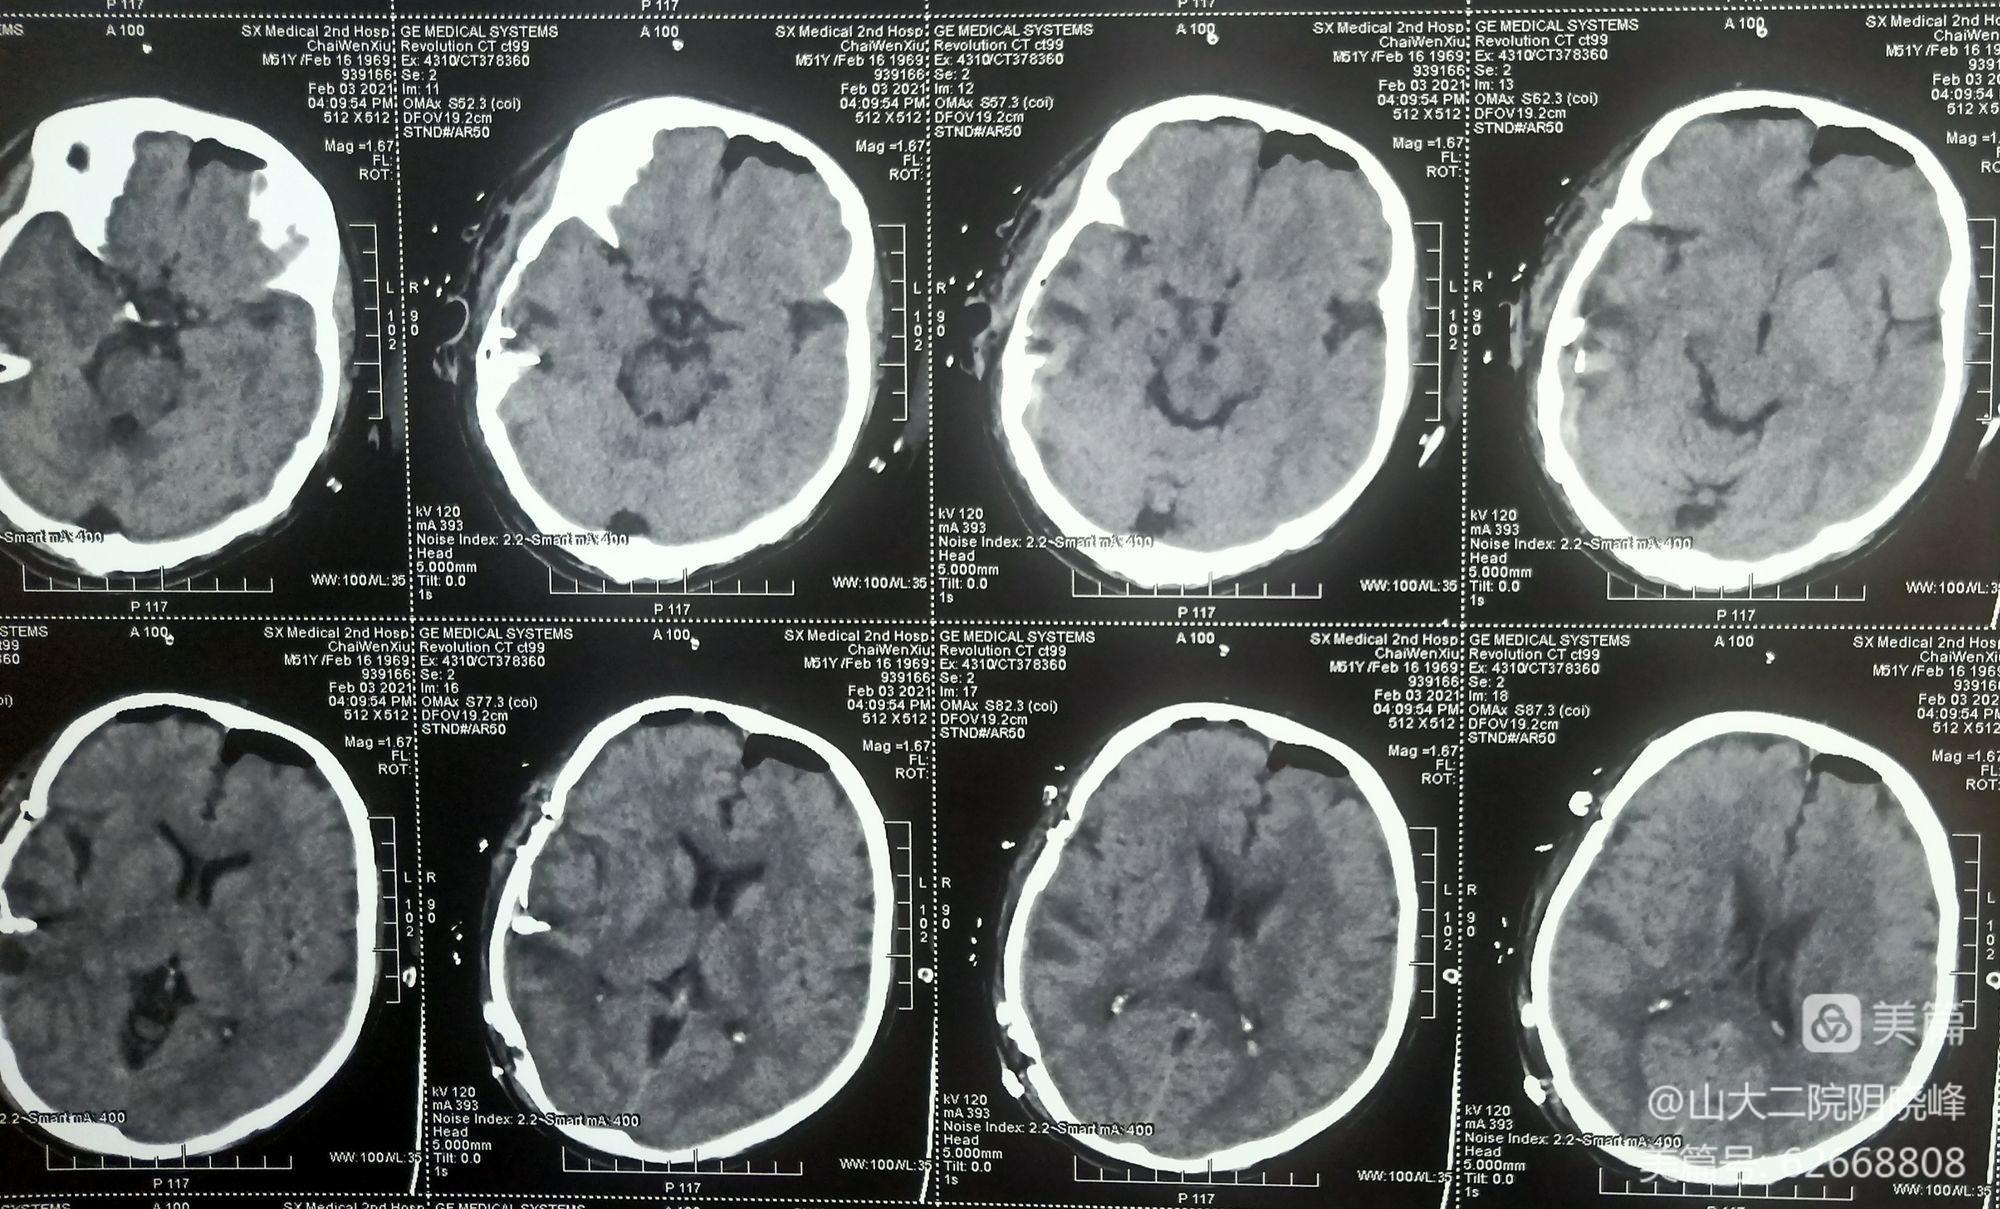

术后第1天复查